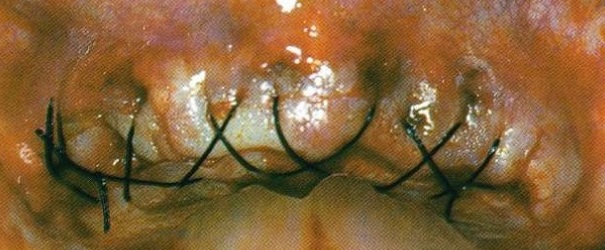

Lors des sutures il très important d’informer le patient s’il s’agit de points de suture ou de points de rapprochement (voir ICI!). Il est très important aussi de dire au patient si le fil est résorbable ou non et en combien de temps il se résorbe (voir ICI!).